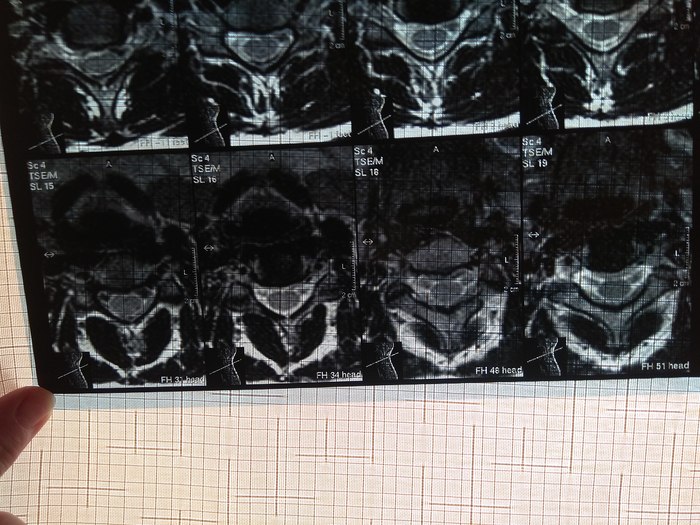

У подруги случилась проблема, тянула с визитом к врачу и в итоге потеряла сознание, вызывали скорую и направили к неврологу. Онемение пальцев на правой руке, сильные боли до судорог и потери сознания. В итоге невролог направил на МРТ и к нейрохирургу, выписали ношение ортопедического воротника, 2 вида уколов и таблетки, названия навскидку не помню. Сказали если через 10 дней не полегчает, то на операцию. Сегодня 5й день, никаких улучшений, рука с каждым днем выше немеет, но подвижность пока в норме. В день по 2-3 раза колет кетонал. Я вот переживаю как бы рука не отказала. Такое может случиться?